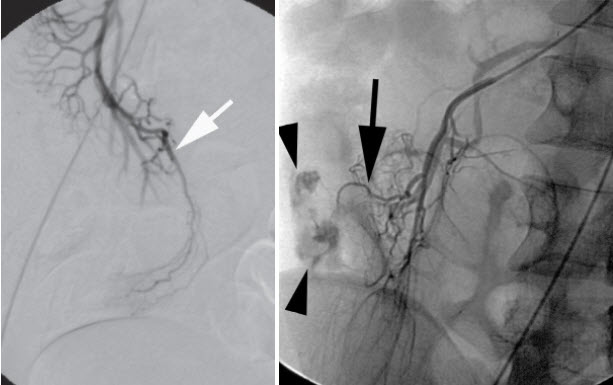

Chụp mạch số hóa xóa nền (DSA):.

Nó chỉ ra các nhánh động mạch mạc treo tràng trên bất thường hay sự thoát mạch của chất cản quang. Động mạch vitelline xuất phát như 1 nhánh hồi tràng của động mạch mạc treo tràng trên. (Hình 4). Phương pháp này có độ chính xác 59%. Hiện tại Bệnh viện của chúng tôi đã có phương tiện này.

2021 09 08 14 15 06

Hình 4. Hình ảnh chụp DSA

* Nguồn: theo Levy A.D.(2004) [7]